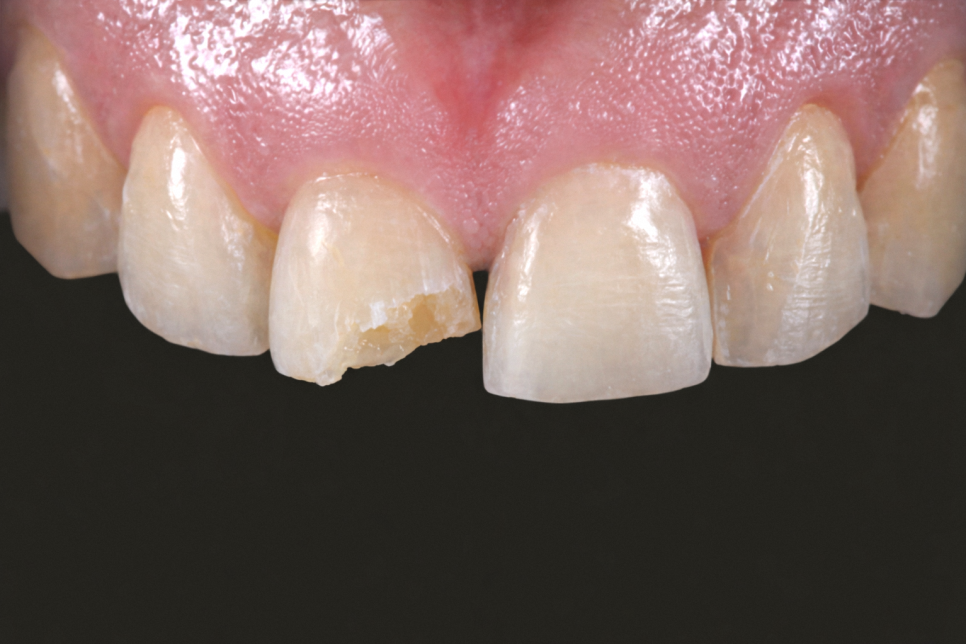

겉으로 보기엔 비슷한 파절도

진단해 보면 깊이가 다른 경우가 많습니다.

그러나 어느 층까지 깨졌느냐에 따라서

지금 느끼는 증상도 필요한 치료도 다릅니다.

- 레진으로 가능한 경우

파절이 법랑질에서 그친 경우에는

레진 수복을 먼저 검토할 수 있습니다.